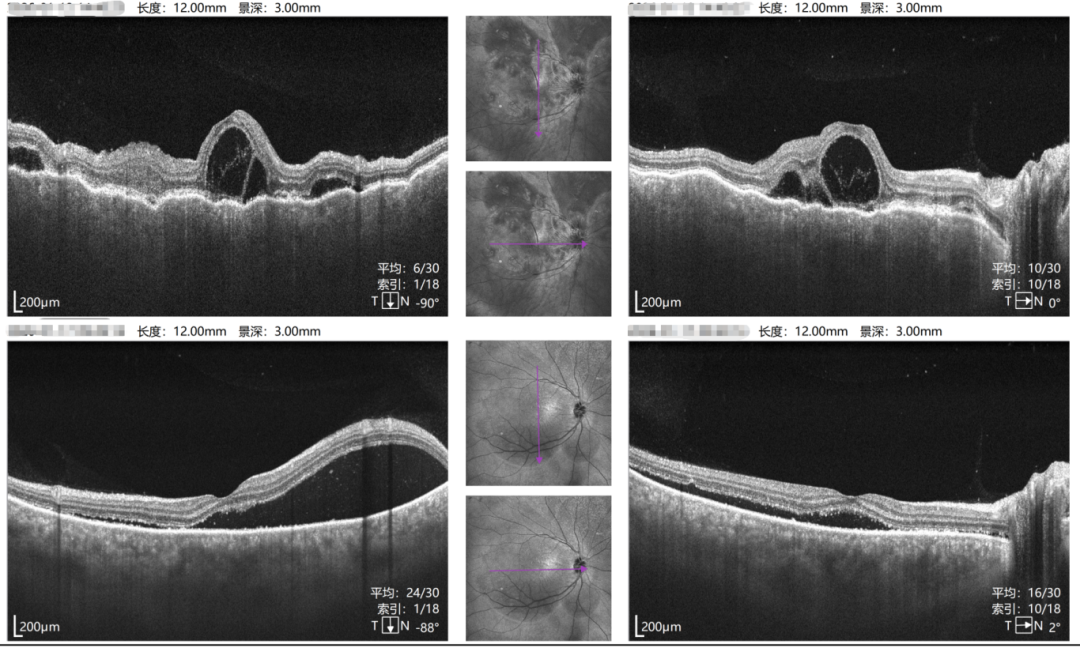

右眼治疗前后对比